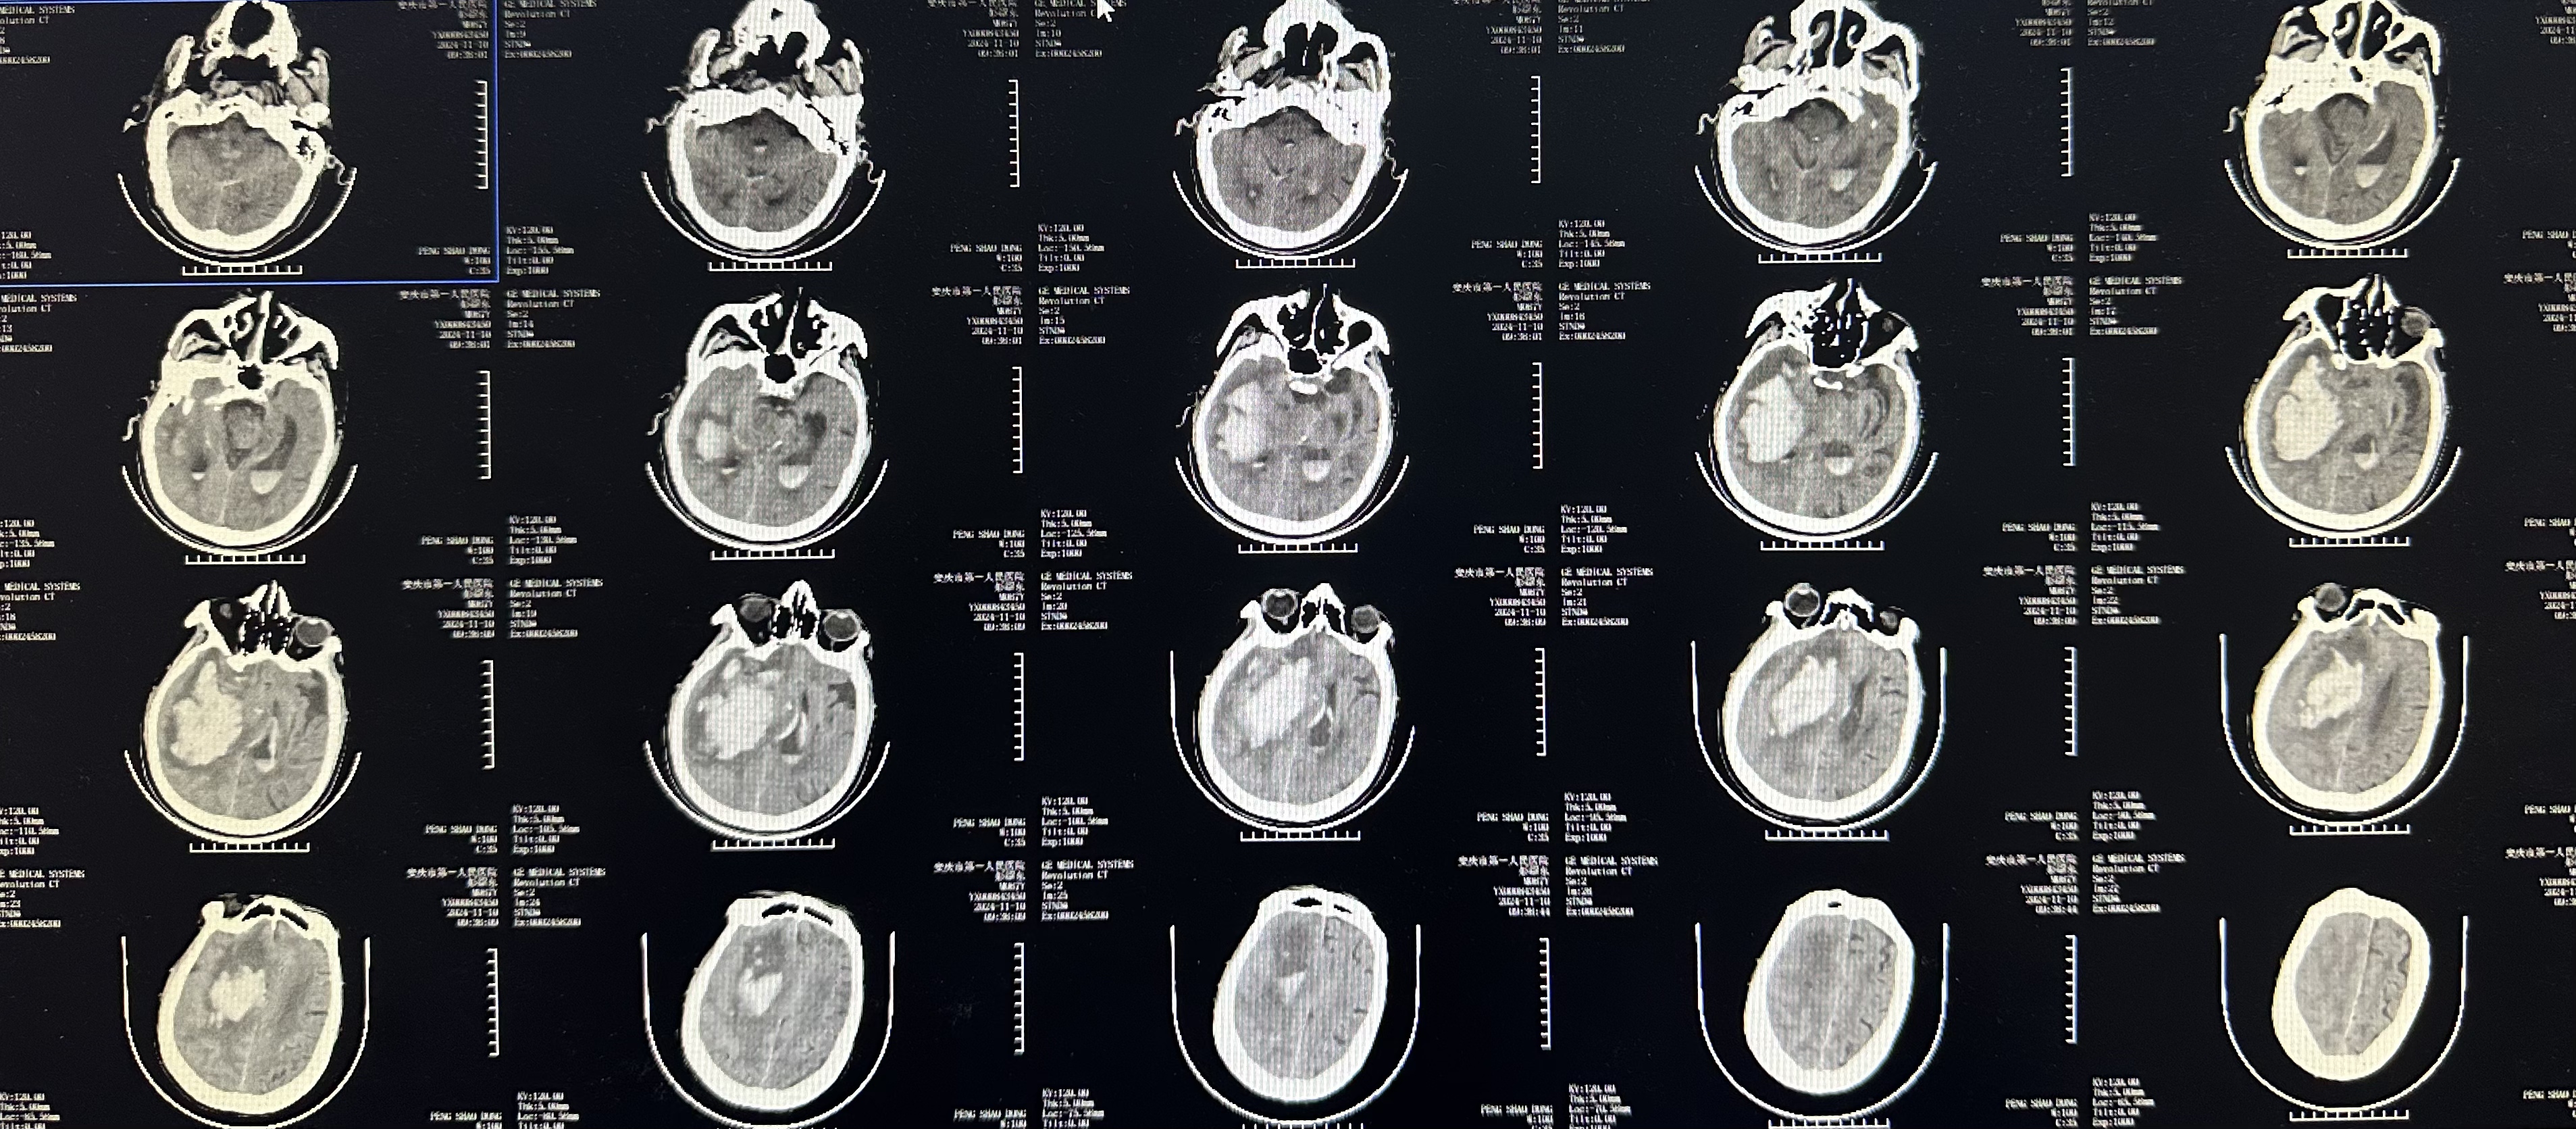

辅助检查:颅脑CT:右侧基底节区出血破入脑室;左侧基底节区软化灶。

术前颅脑CT